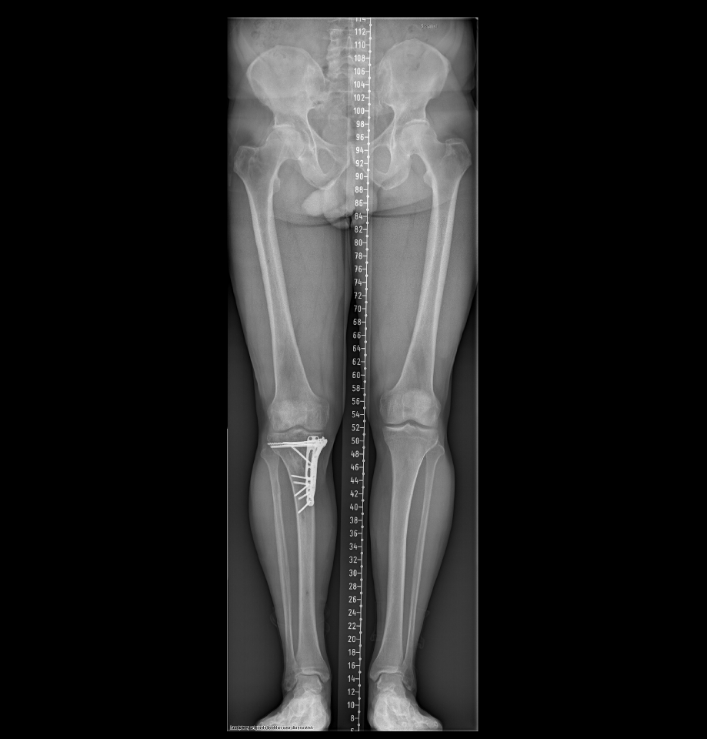

Anhang anzeigen 567019Anhang anzeigen 567020

15-04-2022

Anhang anzeigen 567023Anhang anzeigen 567024

Schrauben raus, geplante Vollprothese Mitte/Ende Dezember 2023, denkbar geheilt, 04-2024. Dann werden es 3 Jahre gewesen sein![]()